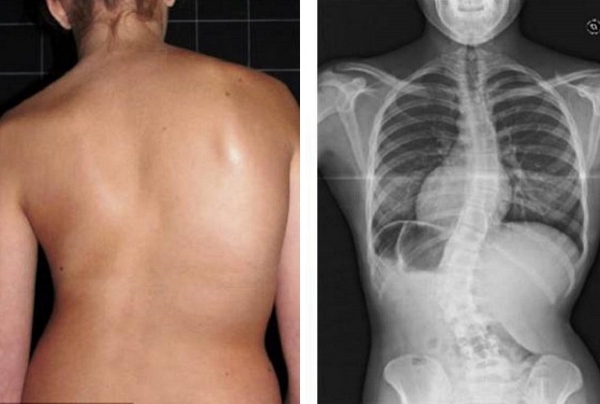

Guardate questa radiografia. È la colonna vertebrale di una persona di soli 44 anni, ma sembra quella di un vecchio. Una volta questi danni si riscontravano dopo i 60 anni, ma oggi è comune per chi ha appena più di 40 anni. Questi cambiamenti progrediscono con l’età, e ignorarli significa rischiare la perdita completa della mobilità!

Guardate queste fotografie. Ecco cosa è successo a coloro che non hanno fatto attenzione ai sintomi. Oggi queste persone sono completamente senza speranza, e molti di loro non hanno nessuno su cui contare per le cure. Volete davvero un destino simile?

— Ognuna di queste persone pensava che non sarebbe mai successo a lei! Ma ecco il risultato: perdita totale di mobilità, paralisi, amputazione — dipendenza a vita dall’aiuto altrui e LA SEDIA A ROTELLE! Più del 90% diventa disabile solo perché non ha preso le giuste misure in tempo. L’USURA DELLE ARTICOLAZIONI INIZIA IN SILENZIO — ignorare il dolore significa buttare la propria vita nel secchio!